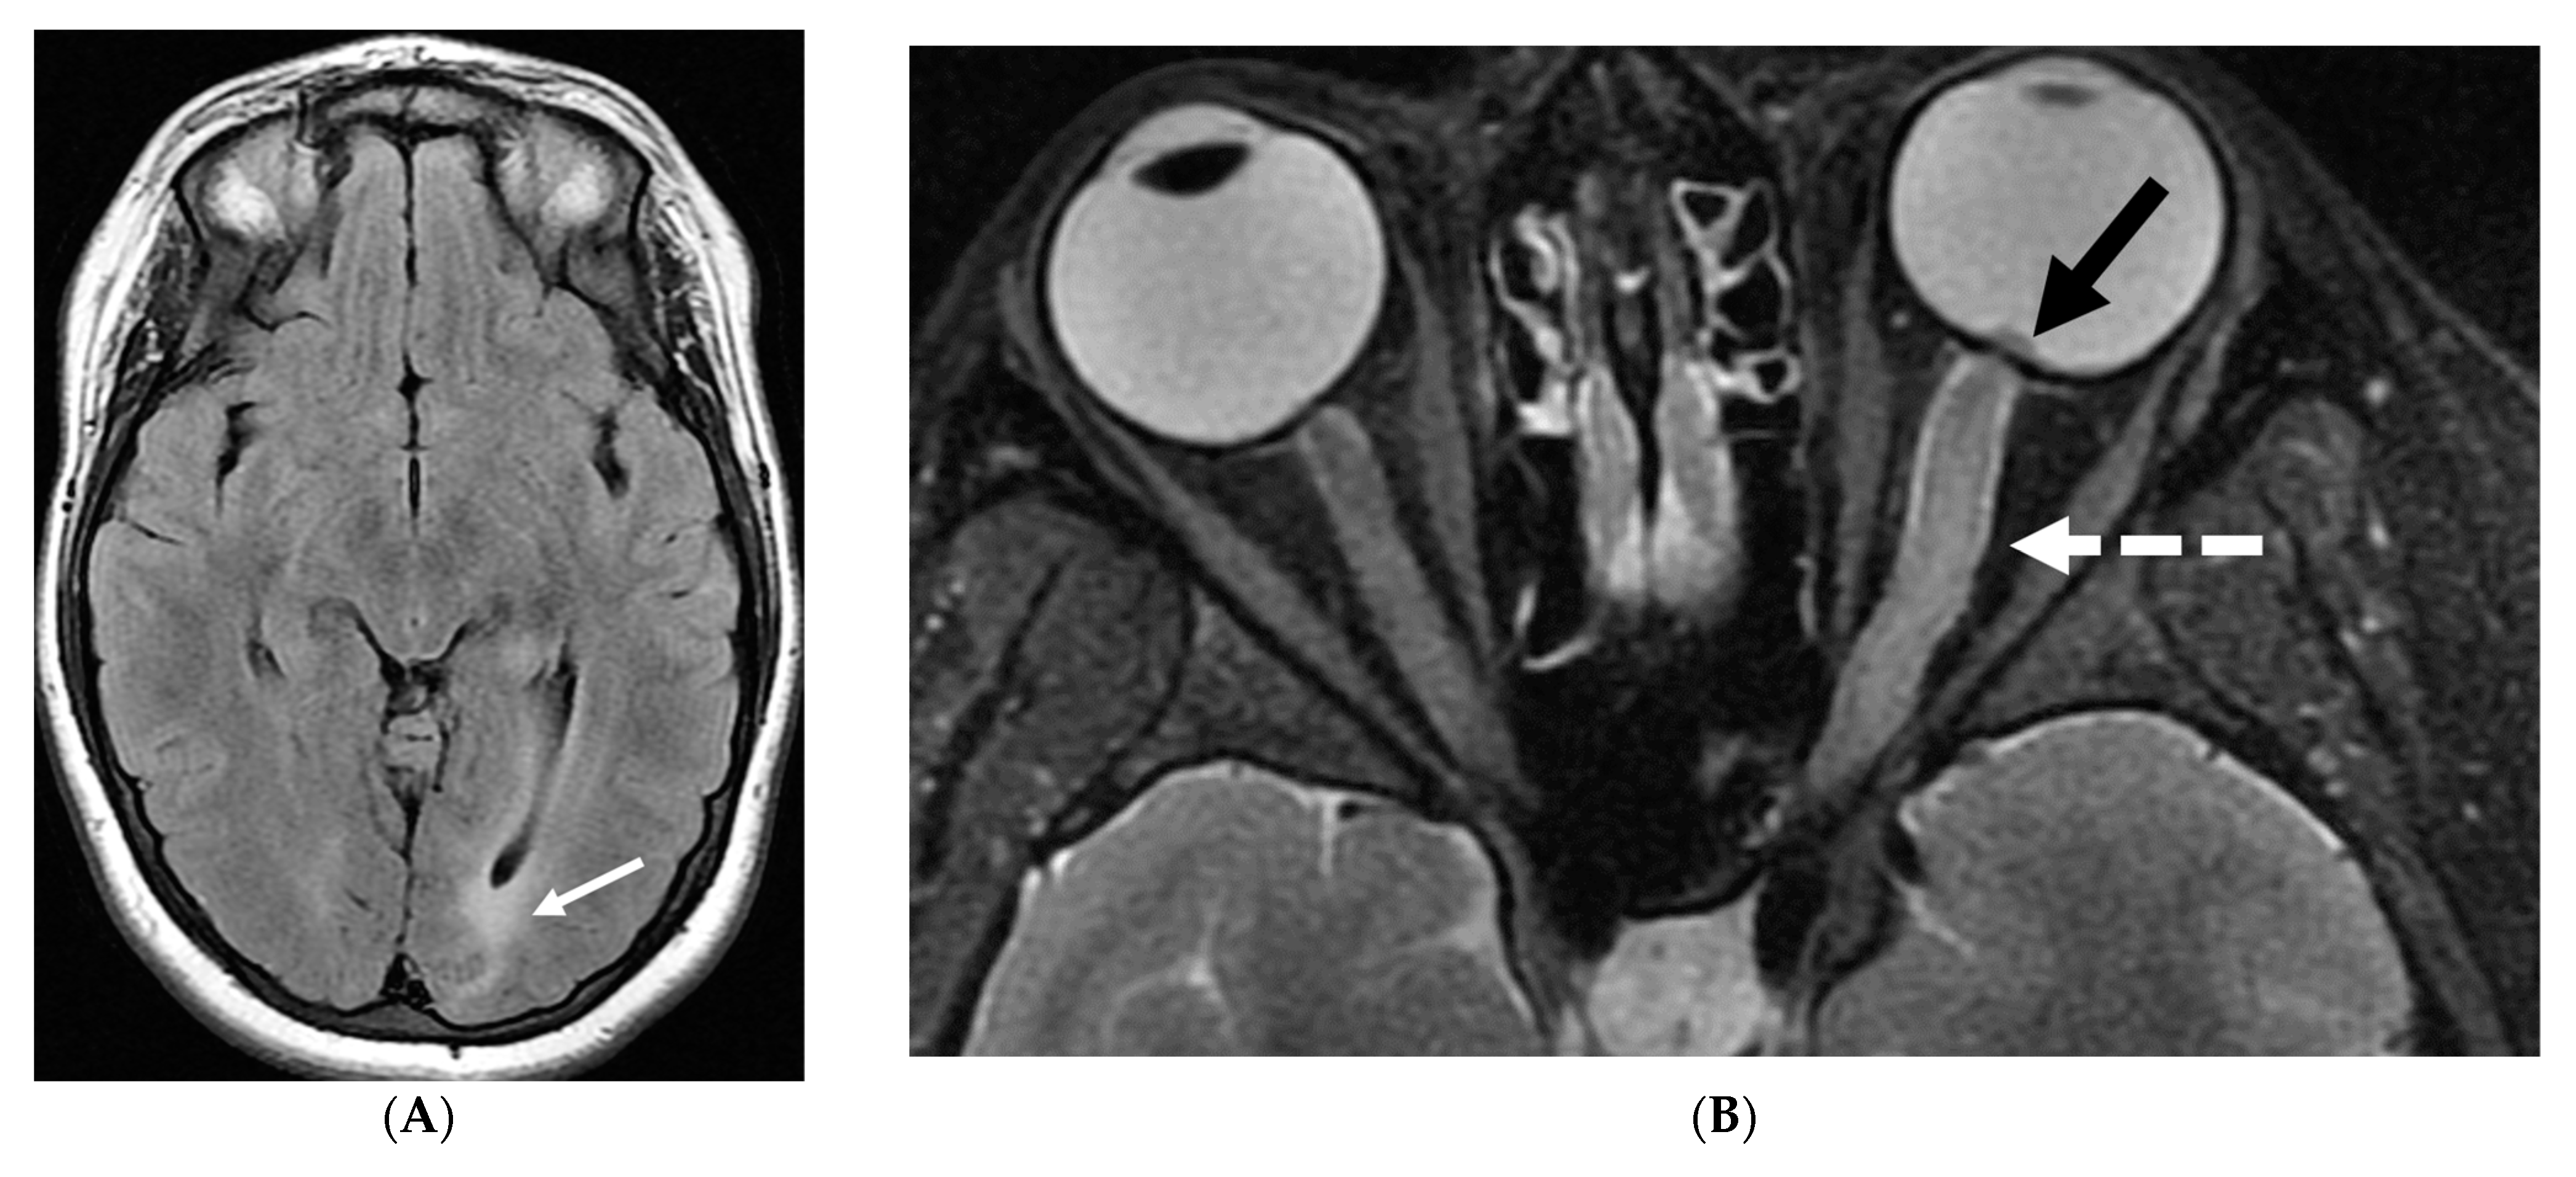

3.2. Neurosarcoidosis

Sarcoidosis is a systemic inflammatory disorder characterized by non-caseating granuloma formation [10,11,12]. Neurosarcoidosis (NS) is uncommon, detected on imaging studies in 15% of the patients, out of which only one-third of them present with clinical symptoms [10,13]. Granulomas, a hallmark of sarcoidosis, can infiltrate cerebral parenchyma, brain vasculature, and cranial nerves [14,15]. Parenchymal involvement leads to motor or sensory deficits, whereas predominant meningeal and subarachnoid involvement leads to cranial nerve deficiencies and vision changes [11]. Contrast-enhanced MRI of the brain and/or the spine is currently considered the standard of care for initial work-up and follow-up in NS [16].

Nodular or diffuse LME, primarily involving the basal meninges, is the most typical finding. It can further spread into the parenchyma via the perivascular spaces [17]. Most cases show focal involvement and are hypointense on T2WI with variable post contrast enhancement [18,19]. Nonenhancing white matter lesions (NEWM), although common, have been shown to have no symptomatic correlation [18]. Optic and facial nerves are frequently involved (Figure 3). The diagnosis of optic neuritis is crucial and regarded as an emergency due to its unfavorable prognosis if not promptly treated [20]. Occasionally [18,21,22], small vessel ischemia related cerebrovascular events occur which manifest clinically with progressive encephalopathy rather than a distinct large vessel stroke [13]. Other rare but important findings include spinal cord and hypophyseal involvement [23]. The mainstay of treatment for CNS sarcoidosis involves corticosteroids to suppress inflammation.

Figure 3.

18-year-old presented with headache, persistent vomiting and weight loss. History of sarcoidosis diagnosed 2 years ago. Axial Fluid Attenuated Inversion Recovery (FLAIR) (A), Axial T1 post contrast (B), Axial T1 inversion recovery post contrast (C) and Coronal Positron Emission Tomograpy (PET) scan (D): There is a heterogeneously enhancing ill-defined area of T2/FLAIR hyperintensity involving the medial aspect of the left globus pallidus (arrows), anterior aspect of the left thalamus and left hypothalamic region. Diffuse enhancement of the basal meninges, tentorium, throughout perisylvian sulci (arrow heads), along the infundibulum, and posteriorly at the craniocervical junction. There is also enhancement along optic nerve sheath (dashed arrows). Features are highly consistent with extensive neurosarcoidosis given the previous history of thoracic sarcoid. PET scan from 2 years earlier demonstrating avid uptake of radiotracer (curved arrows). Radiologically, the differential diagnosis includes tuberculosis and metastatic process. Patient made complete recovery after treatment for sarcoid.